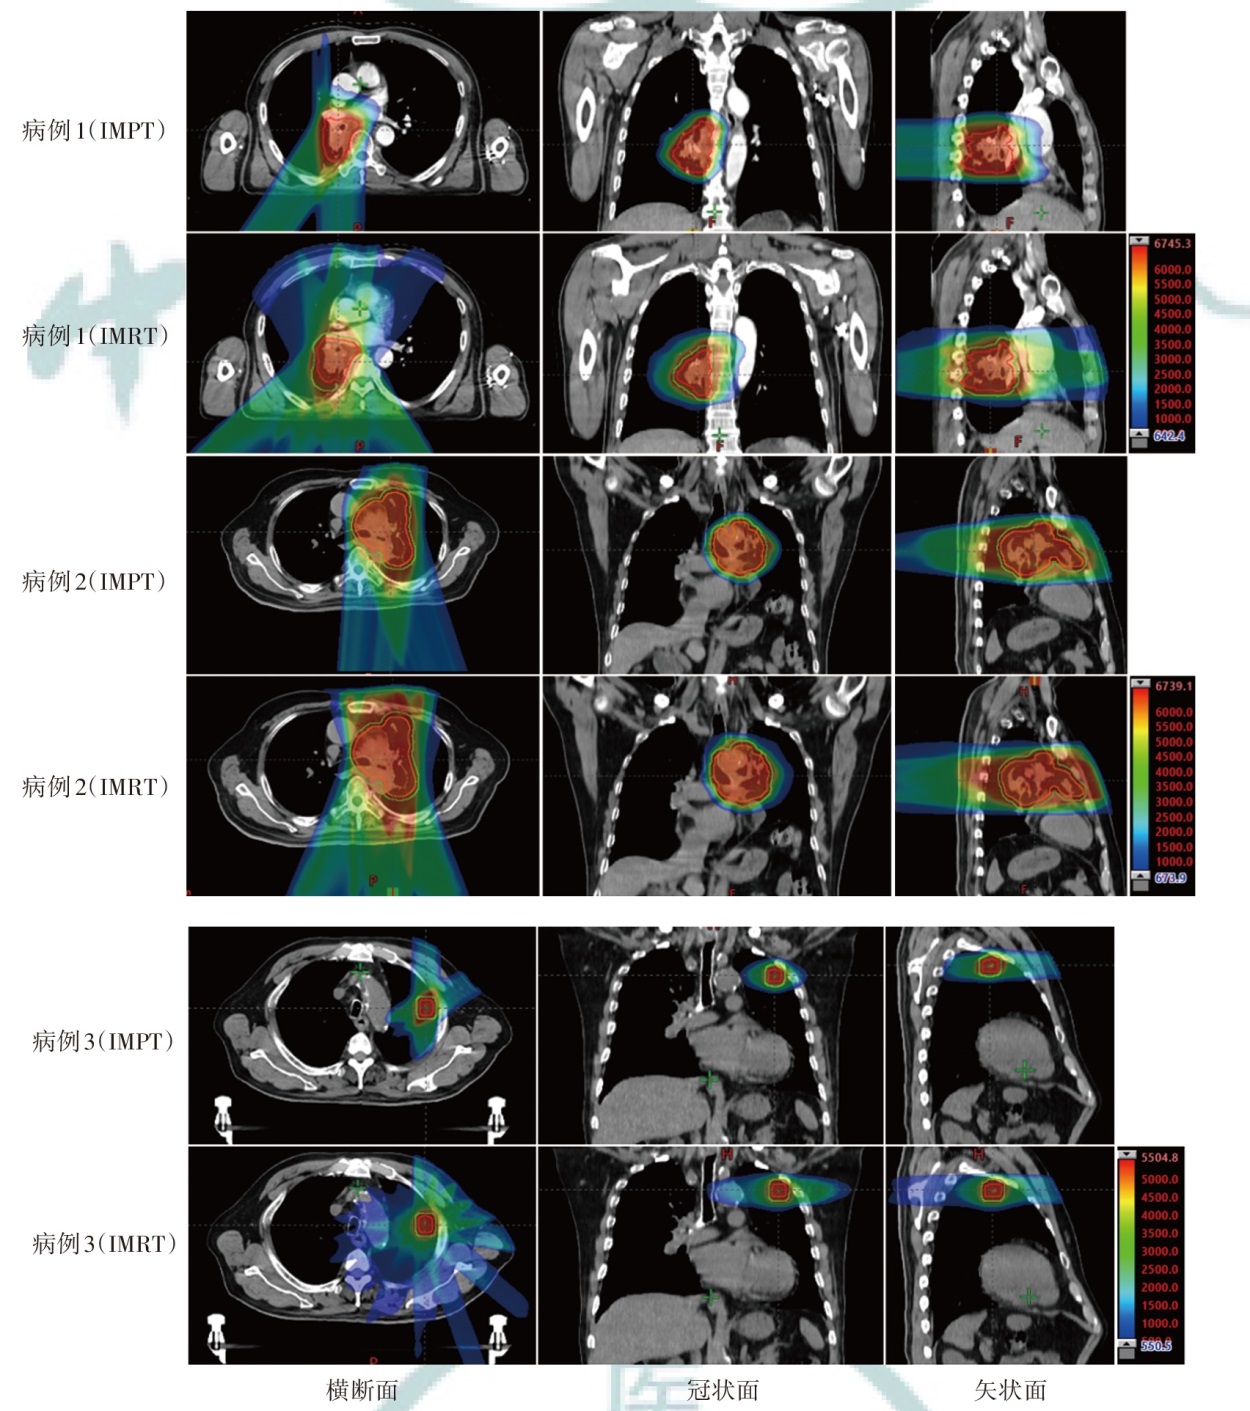

Objective To investigate the dosimetric characteristics of intensity modulated proton therapy (IMPT) and intensity modulated radiation therapy (IMRT) for lung cancers. Methods Three lung cancer patients (central-lower, central, and peripheral types) admitted to Shandong Cancer Hospital and Institute from January 2024 to May 2024 were selected as the research subjects. IMPT and IMRT plans were designed for each case based on the anatomical location of the clinical target volume and the dose constraints for organs at risk (OARs). Dosimetric parameters, including conformity index (CI), homogeneity index (HI), and gradient index (GI) for target coverage, as well as OARs dosimetric parameters were evaluated. The volume of additional dose deposition in the body was compared by assessing regions receiving 10%, 30%, and 50% of the prescription dose. Results For all three cases, IMRT plans demonstrated higher CI values (0.80, 0.60, and 0.79) compared to IMPT plans (0.61, 0.57, and 0.34). IMPT plans yielded lower HI values (0.07, 0.06, and 0.06) than IMRT plans (0.09, 0.15, and 0.09) and lower GI values (2.84, 2.47, and 4.56 vs. 4.91, 3.09, and 4.99 for IMRT plans). Compared with the IMRT plans, the low-dose region in the ipsilateral lung was significantly reduced in IMPT plans (V5 of the IMPT plans were 20.59%, 46.29%, 10.94%, respectively; V5 of the IMRT plans were 48.91%, 60.63%, 19.92%, respectively), but there was no significant advantage in the high-dose region compared to IMRT plans (V20 of the IMPT plans were 12.88%, 34.75%, 5.21%, respectively;V20 of the IMRT plans were 21.70%, 36.50%, 5.31%, respectively). The dose to the contralateral lung and heart was significantly reduced in IMPT plans [the Dmean of the contralateral lung in the IMPT plans were 0.08, 0.04, and 0.00 Gy (RBE), respectively, and those in the IMRT plans were 3.25, 1.18, and 0.55 Gy, respectively; the heart Dmean in the IMPT plans were 6.23, 7.04, and 0.00 Gy (RBE), respectively, while those of the IMRT plans were 18.33, 10.27, and 0.08 Gy, respectively). IMPT plans significantly reduced the volumes receiving 10% of the prescription dose by 65.94%, 25.57% and 72.47%, respectively, compared to IMRT plans. The volumes IMPT plans occupied by 30% of the prescription dose area in the body were reduced by 54.97%, 26.47% and 39.04%, respectively, compared to the IMRT plans. The volumes IMPT plans occupied by 50% of the prescription dose area in the body were reduced by 54.49%, 30.43% and 28.89%, respectively, compared to the IMRT plans. Conclusions IMPT plan significantly reduces the V5 of the ipsilateral lung, the Dmean of the contralateral lung and the heart, while maintaining target coverage compared with IMRT plan for lung cancers. However, IMPT plan does not show much more advantage than IMRT plan in the ipsilateral lung V20. IMPT can reduce the additional exposure volume within the body.